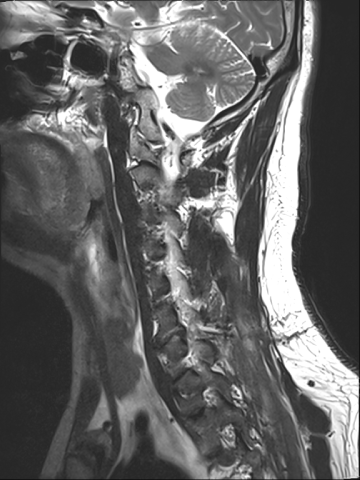

목디스크 수술 치료

2019.05.25

2022.09.13

2022.11.10

2022.11.16